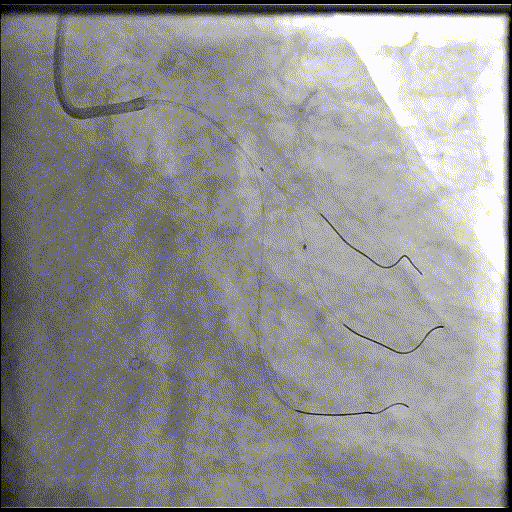

手术经过

导丝到位

当指引导管冠脉开口到位后,选择三根对应导丝分别送入LAD、D1、D2远端。

球囊预扩

选择不同尺寸的预扩球囊逐级预扩张病变,复查造影狭窄减轻不明显。为了解血管真实情况,遂启用IVUS检查。

术前腔内影像学IVUS指导

IVUS提示血管内钙化严重,最小管腔面积不足 4mm²;遂考虑启动IVL治疗。

冲击波球囊治疗

2.5*12mm@4atm 冠脉血管内冲击波导管反复进行8个周期治疗,经IVUS检查提示最小管腔面积增加至4.88mm²;随后选取后扩张球囊对病变行扩张治疗。

支架植入并后扩

于LM-LAD依次植入两枚药物洗脱支架,经非顺应性球囊后扩张支架,复查造影&IVUS提示血管内钙化仍较重,支架贴壁不良,遂再次启动IVL治疗。